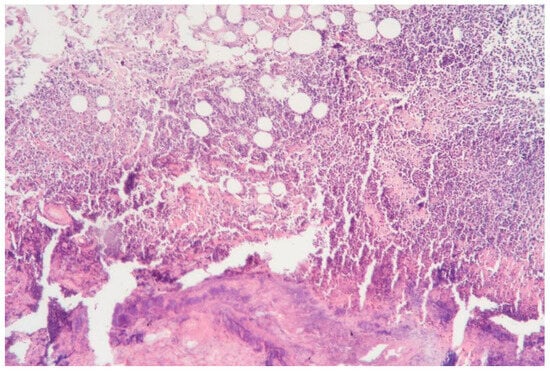

3.1.1. Clinical Case 1: Soft Tissues in the Dissection Area, Scar 10 W (See Figure 2)

Description: The histological examination revealed total necrosis of the epidermis and dermis, with the formation of a demarcation zone heavily infiltrated by polymorphonuclear leukocytes. The infiltrate extended into the subcutaneous adipose tissue. The vessels within the necrotic zone were coagulated, while those in the underlying tissues were markedly dilated. Small diapedesis hemorrhages were noted. The skin appendages in the underlying tissues remained intact, and the collagen fibers were preserved.

Figure 2.

Skin changes in Rat 1 on the 7th day after exposure to the thulium laser at 10 W, 65 Hz. H&E staining, 10× objective magnification.